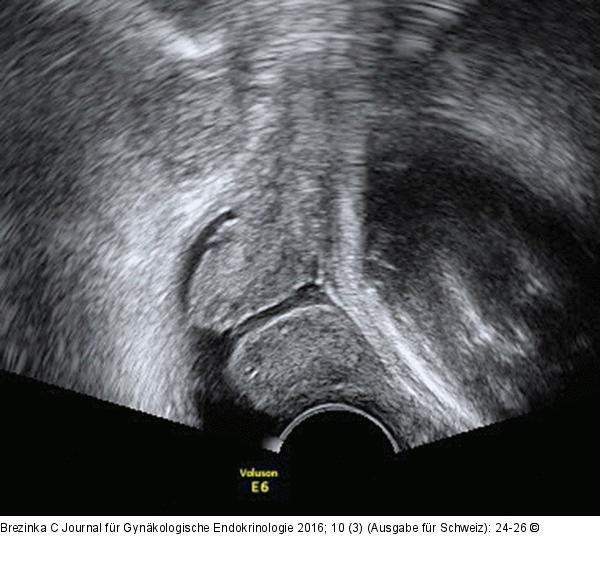

Abbildung 10: Ultraschall-Serometra „Fluid is your friend“ – auch beim geburtshilflichen Ultraschall. Bei einem vorzeitigen Blasensprung in der 36. SSW zeigt sich die Zervix mit 15 mm Länge, noch formiert und erhalten. Das Fruchtwasser geht vom Zervikalkanal in den Fornix vaginae über und macht ein einprägsames Bild. |

Abbildung 10: Ultraschall-Serometra